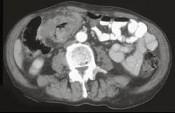

问题 男,45岁,右下腹胀痛、并可触及质硬包块,请结合图像选择最可能诊断 ( )

选项 A.结肠Crohn氏病 B.结肠癌 C.肠结核 D.结肠淋巴瘤 E.慢性溃疡性结肠炎

答案 B